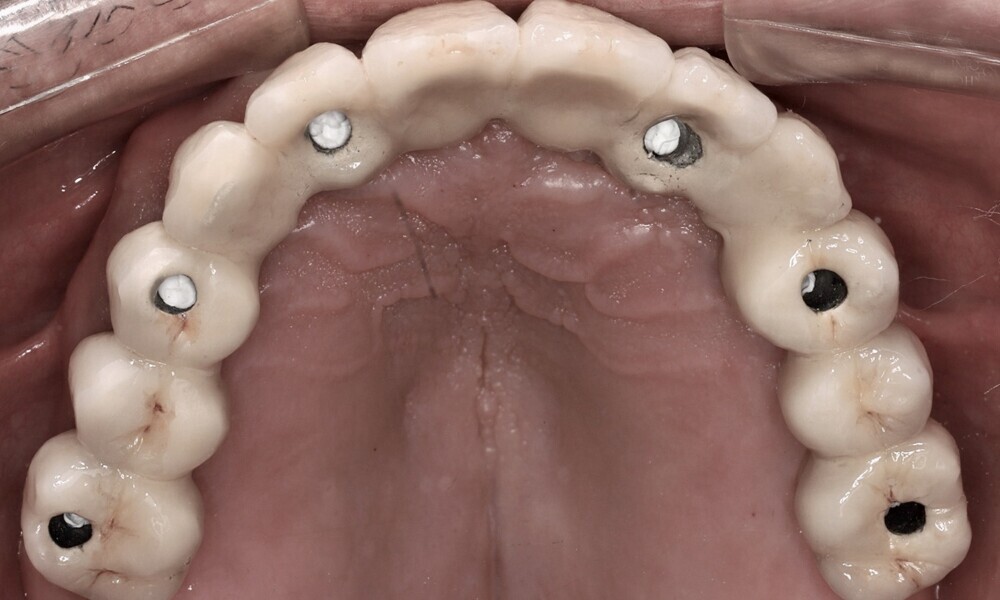

Screw-retained abutments (Straumann) were placed to a torque of 35 N cm as follows (Figs. 32 & 33):

• position #16: RB/wide base (WB); 30°; diameter: 6 mm; gingiva height: 3.5 mm;

• position #14: RB/WB; 17°; diameter: 6 mm; gingiva height: 3.5 mm;

• position #12: RB/WB; 17°; diameter: 6 mm; gingiva height: 3.5 mm;

• position #22: RB/WB; 17°; diameter: 6 mm; gingiva height: 3.5 mm;

• position #24: RB/WB; straight; diameter: 6 mm; gingiva height: 3.5 mm; and

• position #26: RB/WB; 30°; diameter: 6 mm; gingiva height: 3.5 mm.

Four months later, we proceeded with the final prosthetic procedure based on clinical and radiographic evidence confirming osseointegration. The case was completed using Straumann RevEX scan bodies for a full monolithic design with a completely digital workflow. First, an intra-oral scan of the opposite arch was taken, followed by an intra-oral scan with the screwed-in temporary abutments. An intra-oral bite scan and an intra-oral scan of the soft tissue with the screw-retained abutments in place were then taken. The reverse scan bodies were attached to the provisional prosthesis, which was scanned extra-orally. Next, the prototype and verification jig were designed, followed by the milling of the prototype and verification jig (Figs. 45 & 46).

During the next visit, the milled prototype and verification jig were tried in, and the design and manufacturing of the final prosthesis were completed (Figs. 47 & 48). The final abutment utilised was Variobase for bridge (Straumann), placed on top of the screw-retained abutments. The material chosen for the final prosthesis was monolithic zirconia (Figs. 49 & 50).

The delivery of the final prosthesis was then performed, and the aesthetics, occlusion and function were verified (Figs. 51–55). The panoramic control radiograph showed that all measurements were within expected ranges (Fig. 56).